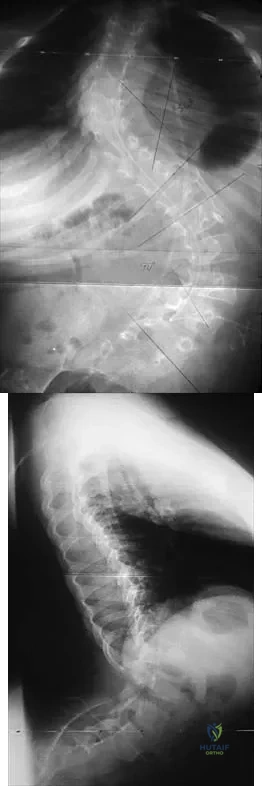

Question 46

A 21-year-old woman who was wearing a seat belt sustained an injury of the thoracolumbar junction in a motor vehicle accident. The AP radiograph shows widening between the L1 and L2 spinous processes, and the CT scan shows the empty facet sign at this level. The initial evaluation should include

Explanation